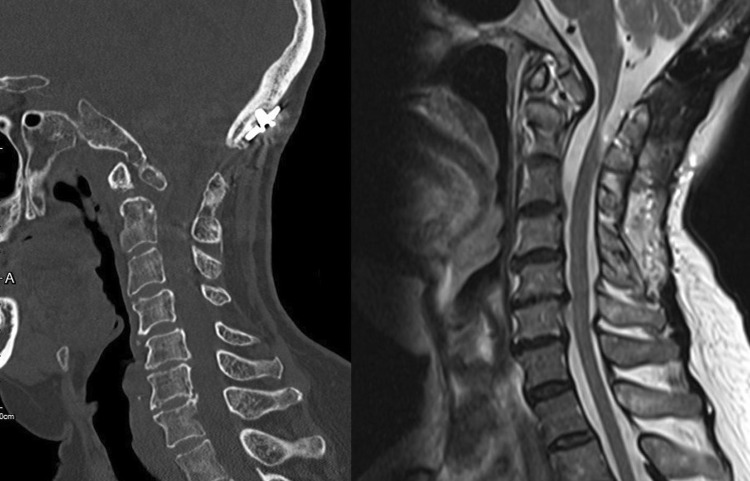

Fig. 3.

Computed tomographic scan of cervical spine in midsagittal view showed dystopic type of os odontoideum and posterior atlantoaxial subluxation. Anterior osteophyte formation of the vertebral bodies with narrowing of intervertebral disc space. The measurement of PADI, the distance from posterior surface of dens to anterior surface of posterior arch of C1, was 12 mm

Fig. 4.

Magnetic resonance imaging of T2-weight midsagittal view showed high signal within the cord on T2WI from C1 to C2 level with significant spinal cord compression at the same level and generalized anterior osteophyte formation, intervertebral disc height narrowing, and vertebral endplate sclerosis from C2 to C7 levels (grade 3)

Fig. 10.

Postoperative computed tomographic scan of cervical spine in midsagittal view (left panel) and postoperative magnetic resonance imaging of T2-weight midsagittal view (right panel) revealed no spinal cord compression at the atlantoaxial area after laminectomy of posterior arch of C1 and iliac crest graft was fused from occiput to the spinous process of axis